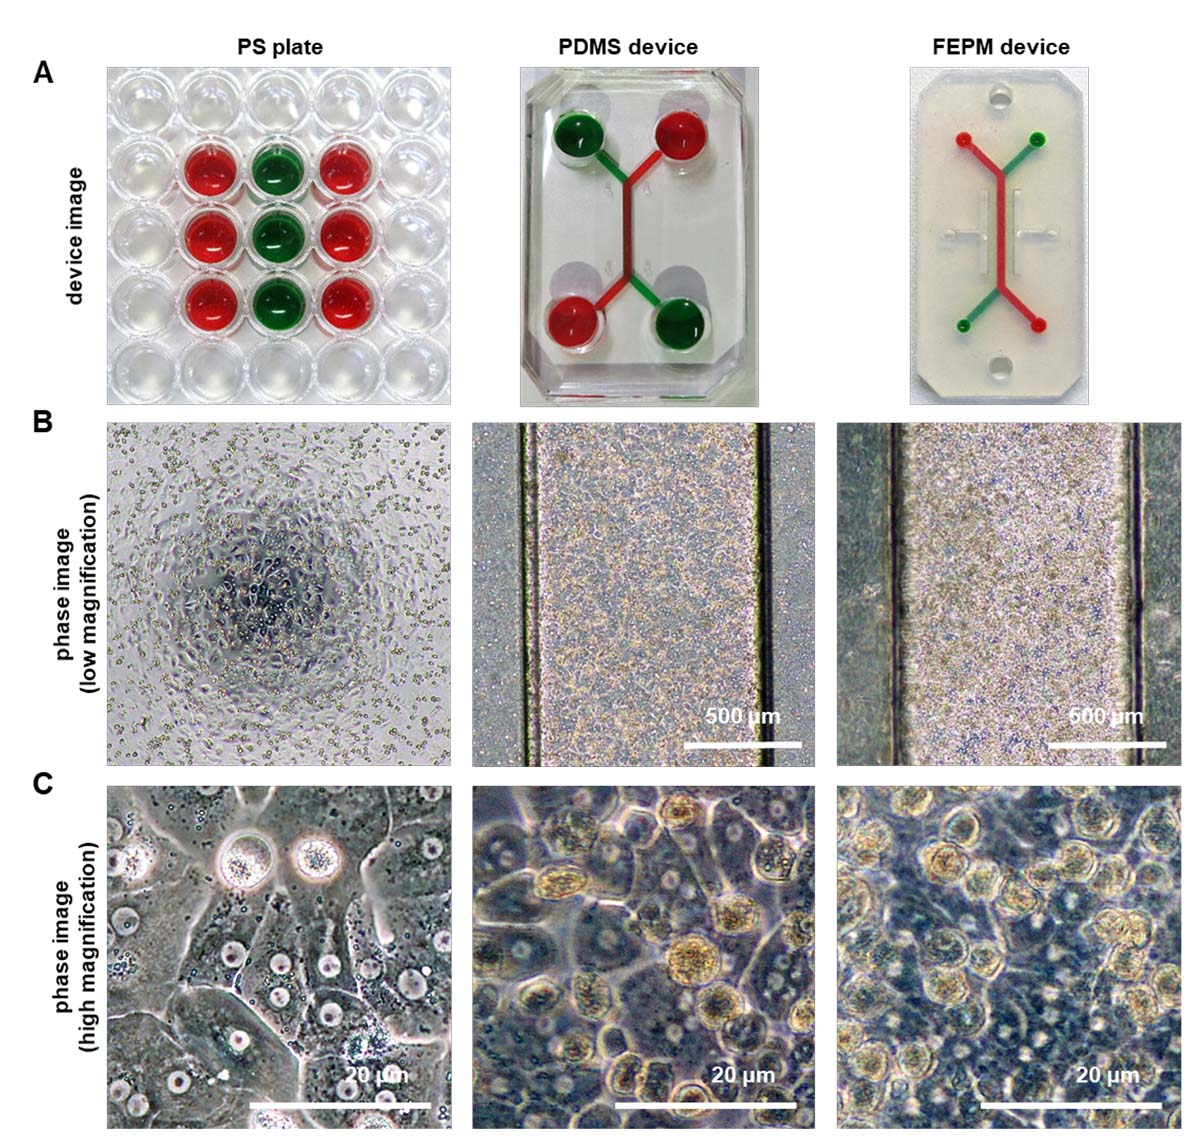

フッ素系エラストマー素材を用いた肝臓チップの開発と薬物代謝・毒性試験への応用

フッ素系エラストマー製マイクロ流体デバイスを用いた肝臓チップを作製可能であることを確認した。フッ素系エラストマー製肝臓チ...